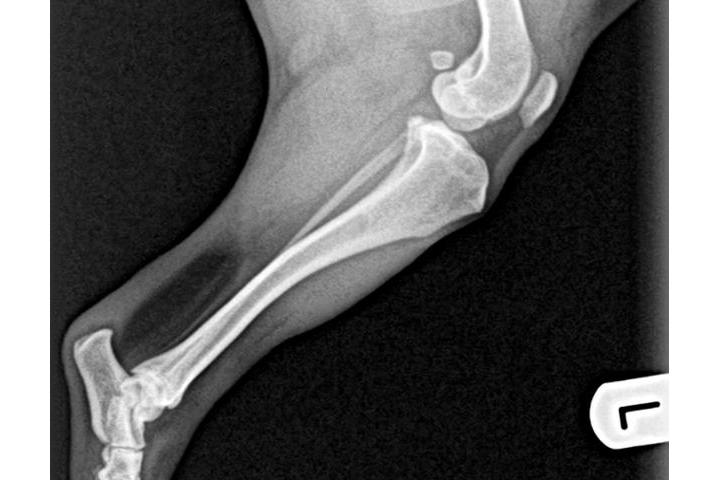

le 30/05/2017 à 17:51h

2a radio

Tengo buenas no tan buenas noticias...la adopción legal de Sólo se ha resuelto....ya es oficialmente nuestra....rstamos a la espera de la documentación para realizar el cambio de demarcación y censarla en Reus...por otro lado la visita al veterinario y las rx confirmaron el diagnóstico inicial...el grado de luxación de sus rótulas es muy grave y la cirugía es inevitable....estoy a la espera del informe del traumatólogo y del nuevo presupuesto para haceroslo llegar a todos; si bien es algo más económico que los dos anteriores sigue subiendo un pico. Habrá que operarprero una para y esperar para posteriormente operar la otra..de ese modo podrá llevar una vida relativamente normal hasta su total recuperación....la buena noticia es que no hay indicios de artrosis lo que significa que no hay dolor...una vez iniciado la primera intervención se valorará es estado de sus tendones para descartar un "tendón laxo"...a lo largo del día recibiré por mail el informe completo junto con una copia de las rx para poder mostraroslas....de nuevo gracias a todos por ayudarme a hacer posible el tratamiento de Snoopy